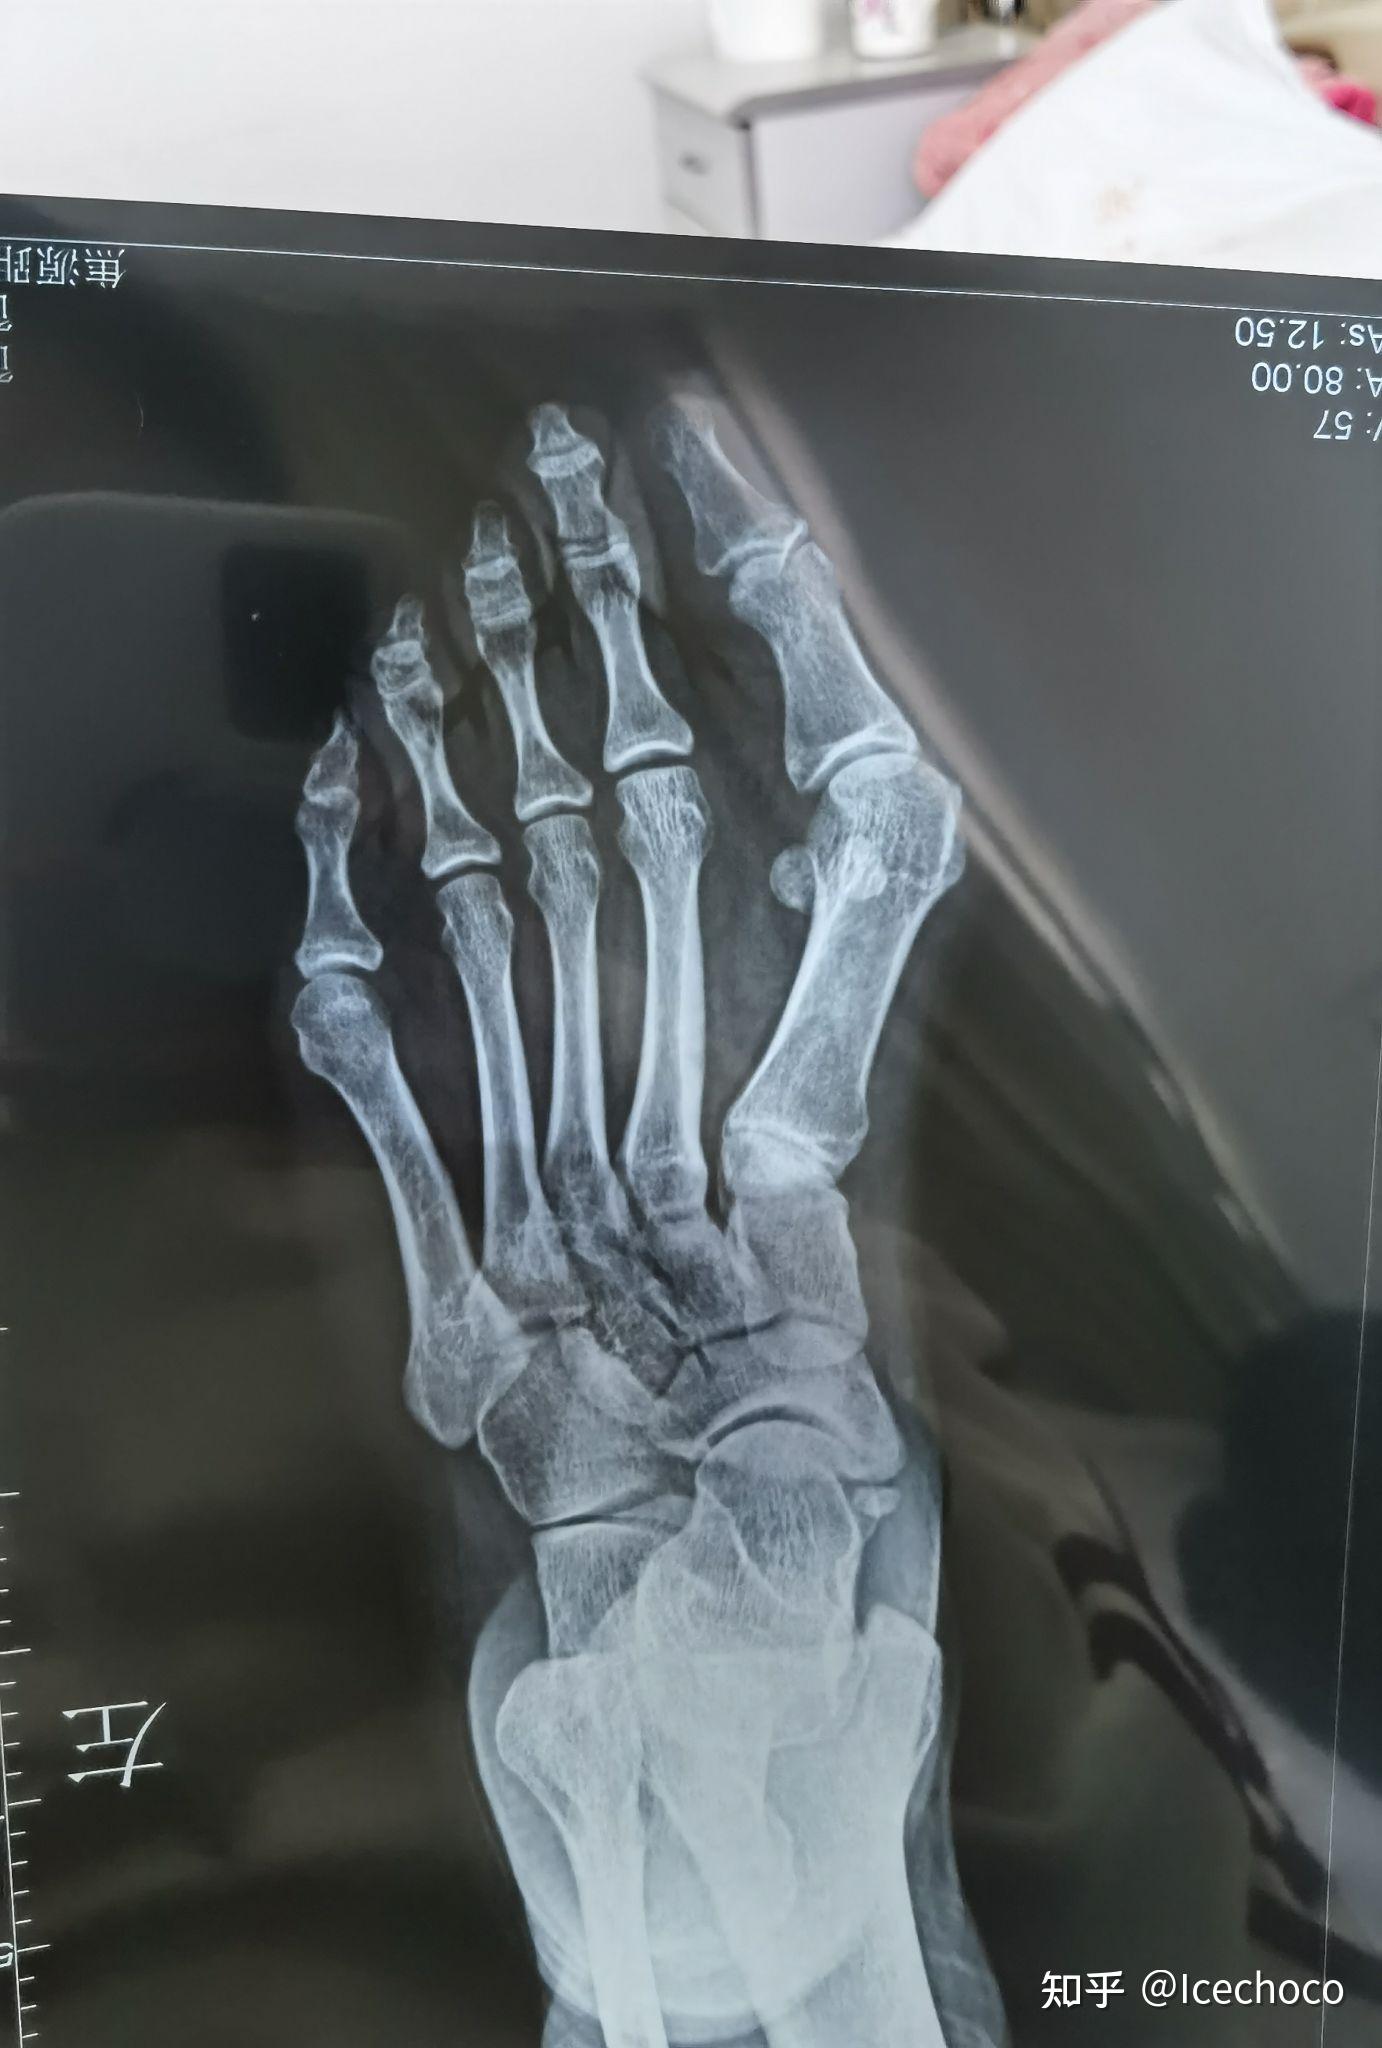

大脚骨(拇外翻)介绍及开展的典型病例

图片尺寸1536x2048